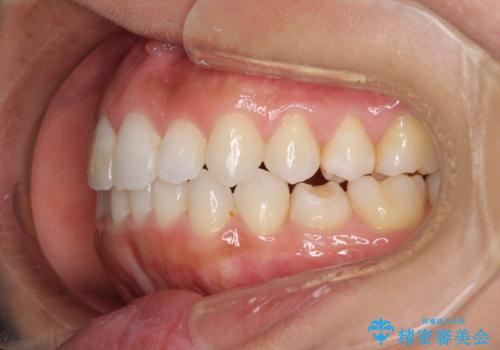

- 上下の前歯のデコボコと奥歯の反対咬合を気にして来院された患者様です。

インビザラインを用い、上下顎ともにIPR(歯と歯の間を削る)により叢生を改善することとしました。

奥歯の反対咬合は、骨格に由来するものであるため、改善できるところまで改善していくこととしました。

治療を長期化させたくないとのご要望があったので、左下の90度捻転した歯は、捻転した状態のゴールとしました。

反対咬合を改善したことで、歯ぎしりしたときの引っかかる感じがなくなり、奥歯への負担を大きく軽減することができました。